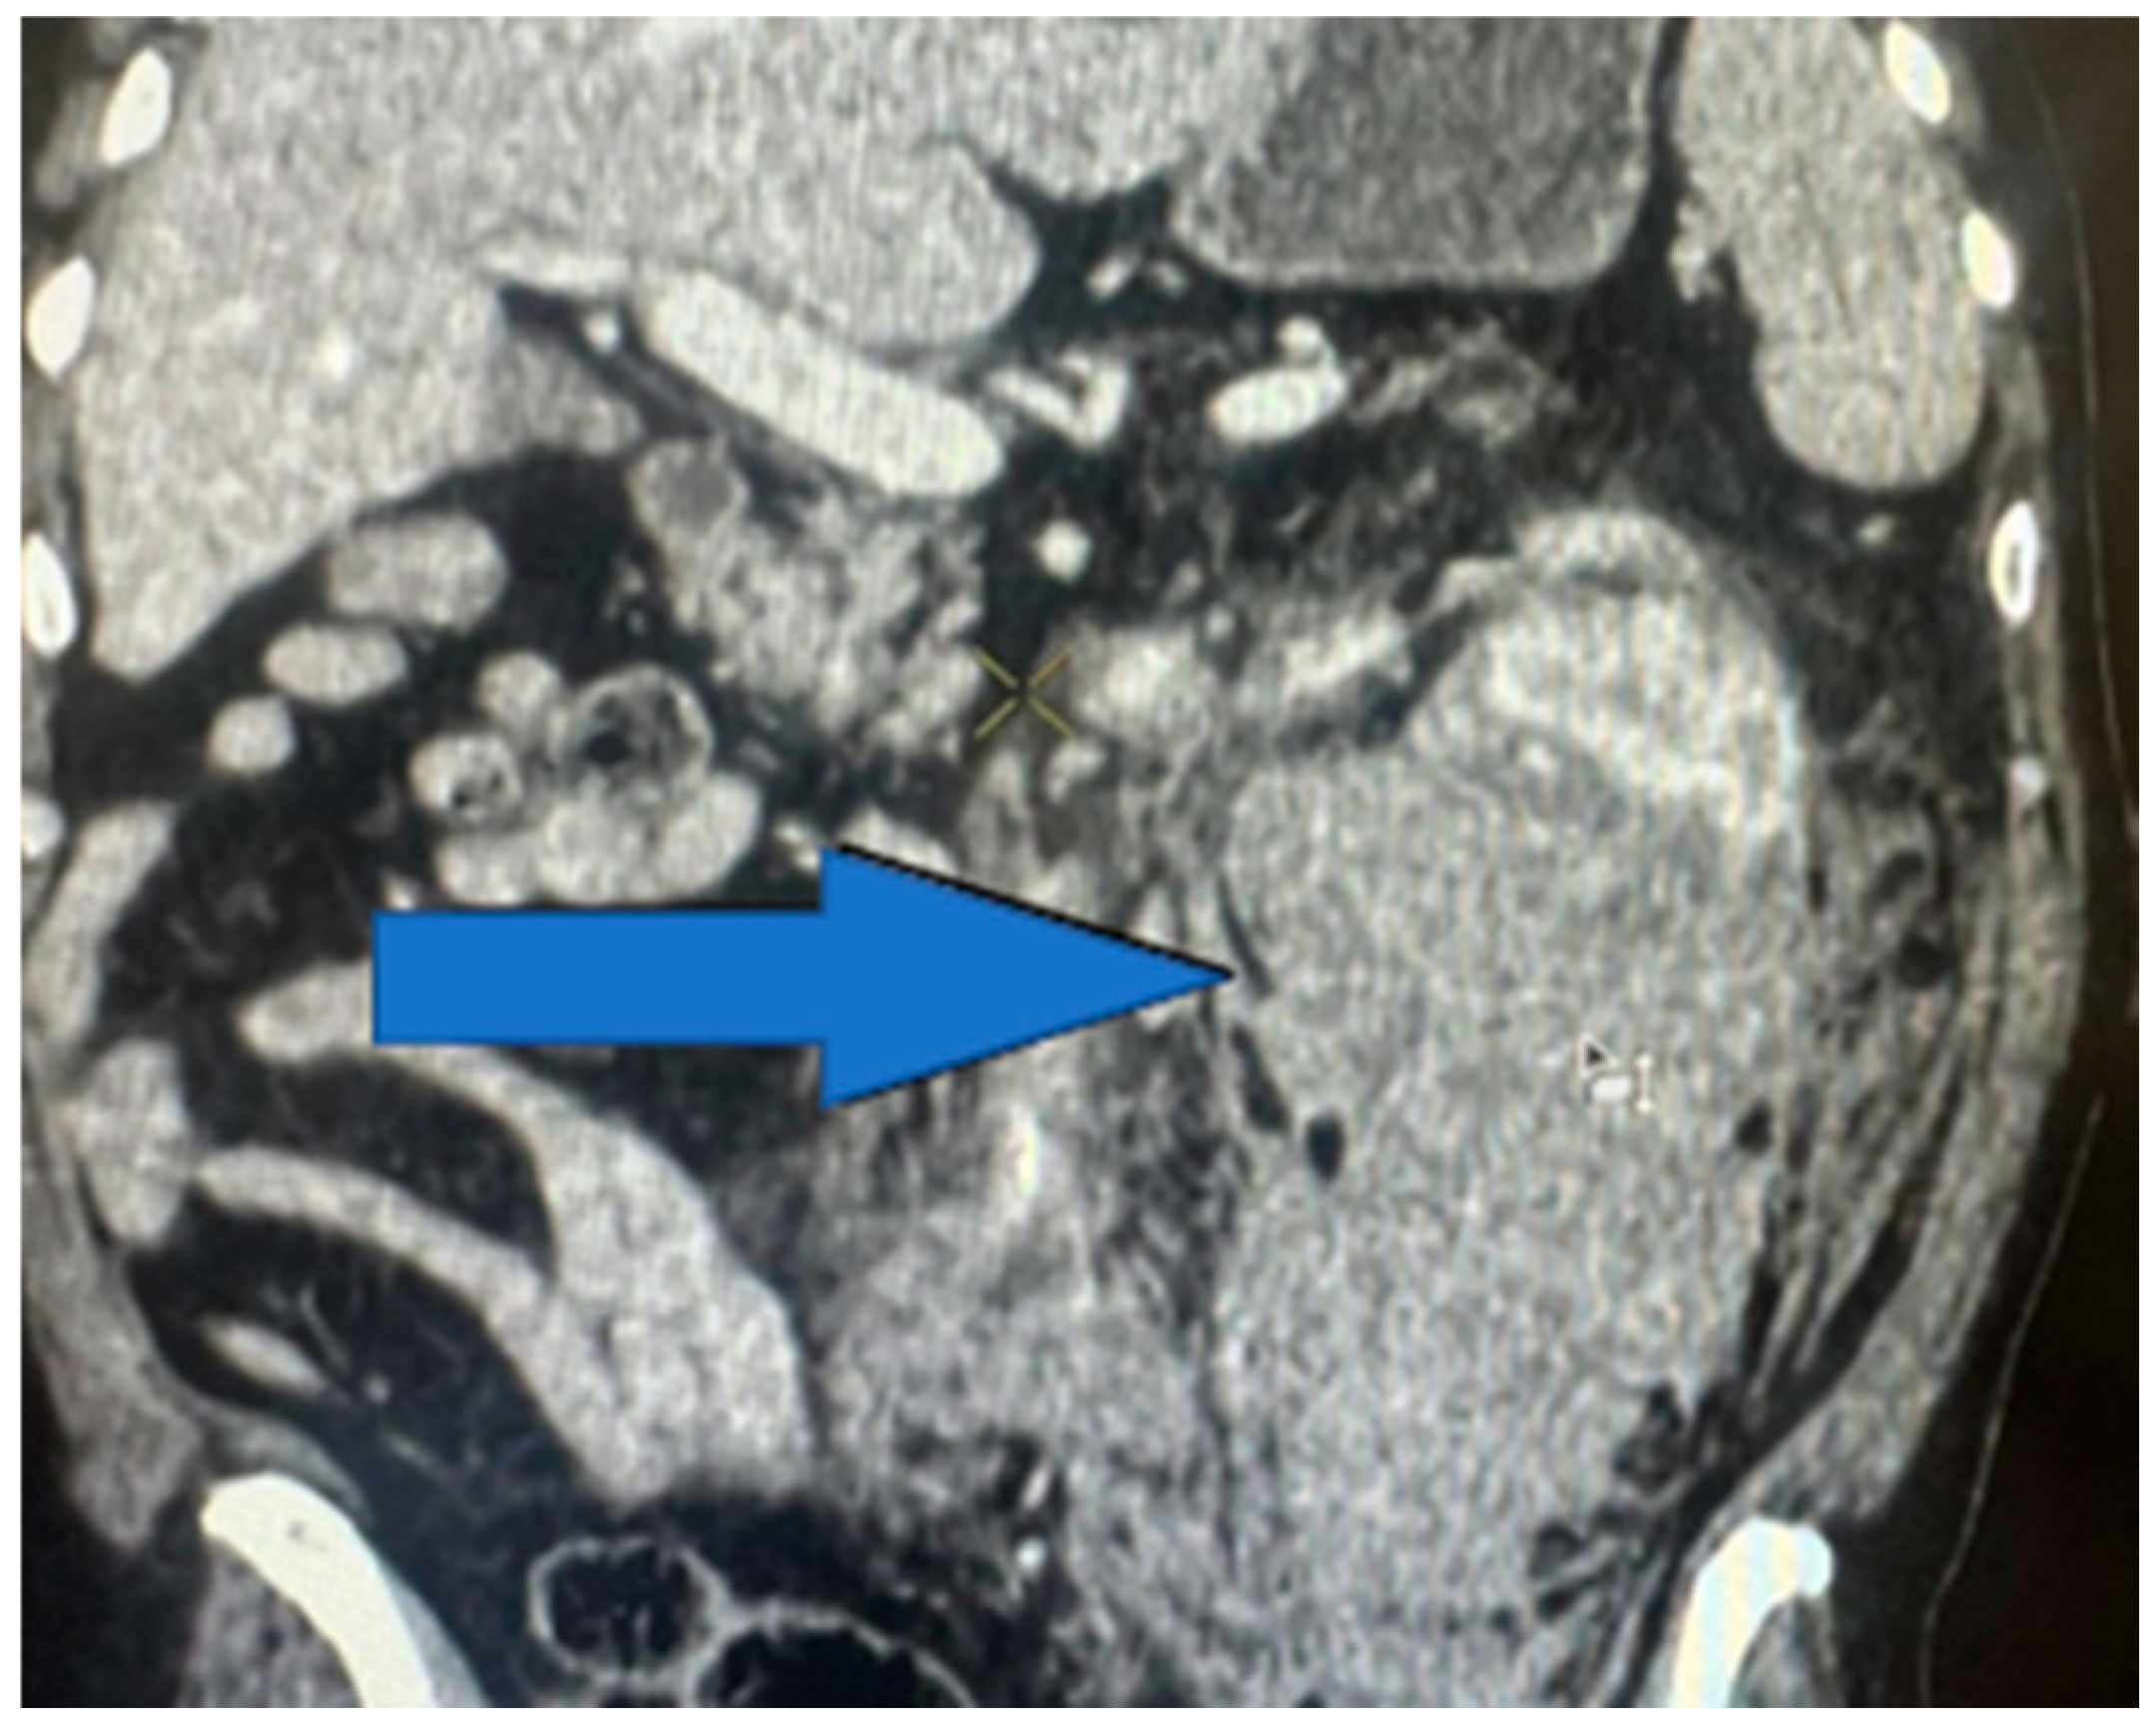

The distribution of the renal injuries, according to AAST classification (Figure 5), in this study is the following: grade 1 (Figure 6) (26.97%), grade 2 (Figure 7) (34.83%), grade 3 (Figure 8) (19.10%), grade 4 (Figure 9) (10.11%), and grade 5 (Figure 10 and Figure 11) (8.99%).

Figure 11. Contrast-enhanced CT scan showing left-kidney grade 5 injury—avulsion of renal hilum with large hematoma, coronal section.